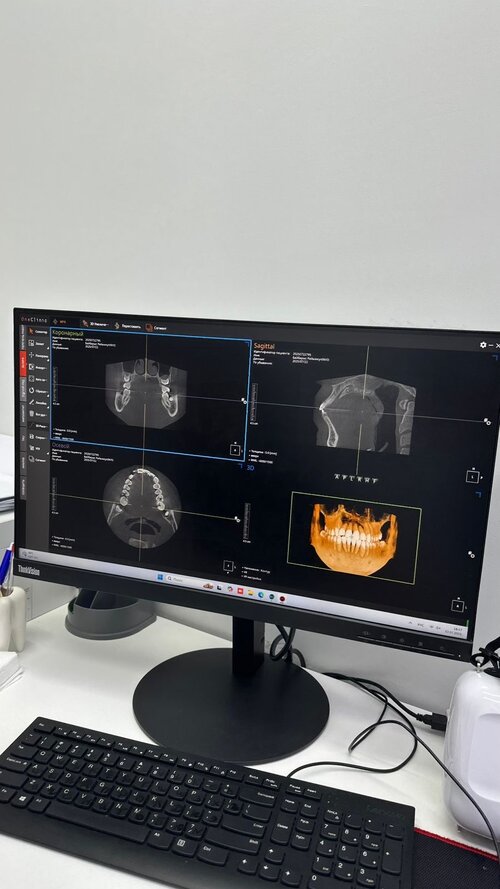

I went to the dentist today and got a pano scan of my teeth. And my dentist is saying I must remove all 4 wisdom teeth cuz they ain’t growing properly. I also have bimaxillary protrusion (I also have a x-ray scan of that). Also, to fix the protrusion they are saying they might use a pallet expander and then put braces. What do yall think? Will the extraction of 4 wisdom teeth and a pallet expander help me? 2 other doctors said I need to extract a tooth from all 4 sides or grind each teeth bit by bit in order to fix my protrusion and then put braces but I don’t like that idea. What do yall think and recommend me to do? And how will my face change by doing all these things? Oh and also my face will be really swollen after my wisdom teeth extraction, is there anything I can do about that?

IMG_1260.jpeg5.8 MB · Views: 0

8aff9cc3-5597-436d-bbde-c33b12560c18.jpeg275.9 KB · Views: 0

8aff9cc3-5597-436d-bbde-c33b12560c18.jpeg275.9 KB · Views: 0 -